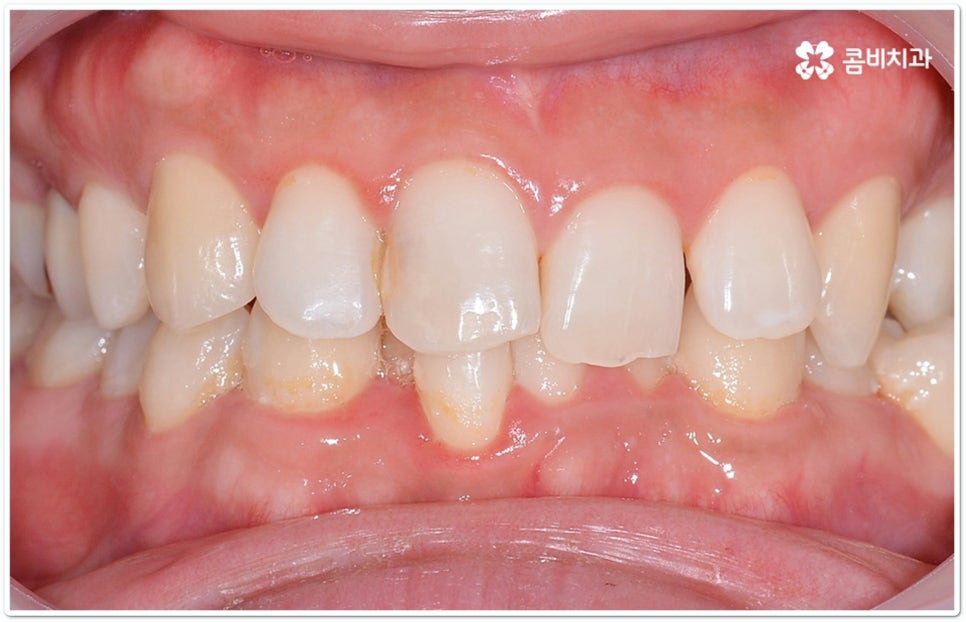

특히 클리피씨교정 장치는 전체 치료 기간을 단축시키고 치아 이동 통증 역시 감소시켜 주기 때문에 요즘 가장 많은 분들이 선호하고 있어요. 물론 자세한 교정 치료 과정은 환자분들마다 달라지므로 꼼꼼한 검진 및 상담을 통해 맞춤 교정 계획을 세우는 것이 무엇보다 우선시 되어야 할 것이나 장치 자체가 결과에 미치는 영향은 그다지 크지 않은 만큼 현재 가장 널리 쓰이고 있는 클리피씨교정 장치에 대해 알아보는 시간을 가지면 교정 치료를 진행하고자 하실 때 도움이 되실 거예요.

이와는 다르게 클리피씨교정 장치는 자가결찰방식이라고 해서 각 브라켓에 여닫을 수 있는 특수한 클립(뚜껑)이 달려 있어 전체 와이어를 통과시켜 잡아주는 방식을 이용하기 때문에 겉면이 매끄럽고 진료 시간도 짧아지며 마찰로 빠져나가는 교정력을 줄여주어 좀 더 효율적으로 치아를 이동시킨다고 할 수 있어요. 즉 보다 적은 힘으로 지속적이고 부드러운 치아 이동을 가능하게 하므로 언급했던 것처럼 개인차가 있지만 전체 기간을 약 6개월 정도 단축시키고 치아가 이동할 때 느낄 수 있는 초기 통증도 감소시켜 줄 수 있는 거예요. 또한 치아 색상과 비슷한 세라믹 재질을 이용하기 때문에 음식을 먹거나 대화를 하는 등 입을 벌렸을 때 보일 수 있는 교정 장치가 그렇게 크게 눈에 띄지 않아 심미적으로도 뛰어나다는 장점을 가지고 있습니다.

예를 들어 심미성도 중요하지만 가격적인 부담을 좀 더 줄일 수 있는 방법이 없을까 싶을 때는 일반 세라믹 교정을 이용하여 교정 치료를 진행할 수 있고 세라믹 브라켓보다 더 심미성이 뛰어나면서도 불편함이나 이물감이 크지 않은 방법은 무엇일까 궁금할 때는 겉으로 보이지 않는 설측교정의 단점을 보완한 콤비교정을 고려해 볼 수 있는 거예요. 이와 같이 환자분들 상황에 맞게 도움을 받을 수 있는 여러 장치들이 있으니 환하고 밝은 미소에 대한 로망이 계속 있으셨다면 더이상 망설이지 말고 정밀 검진과 상담부터 차근차근 진행해 보시길 권유드리고 있습니다.